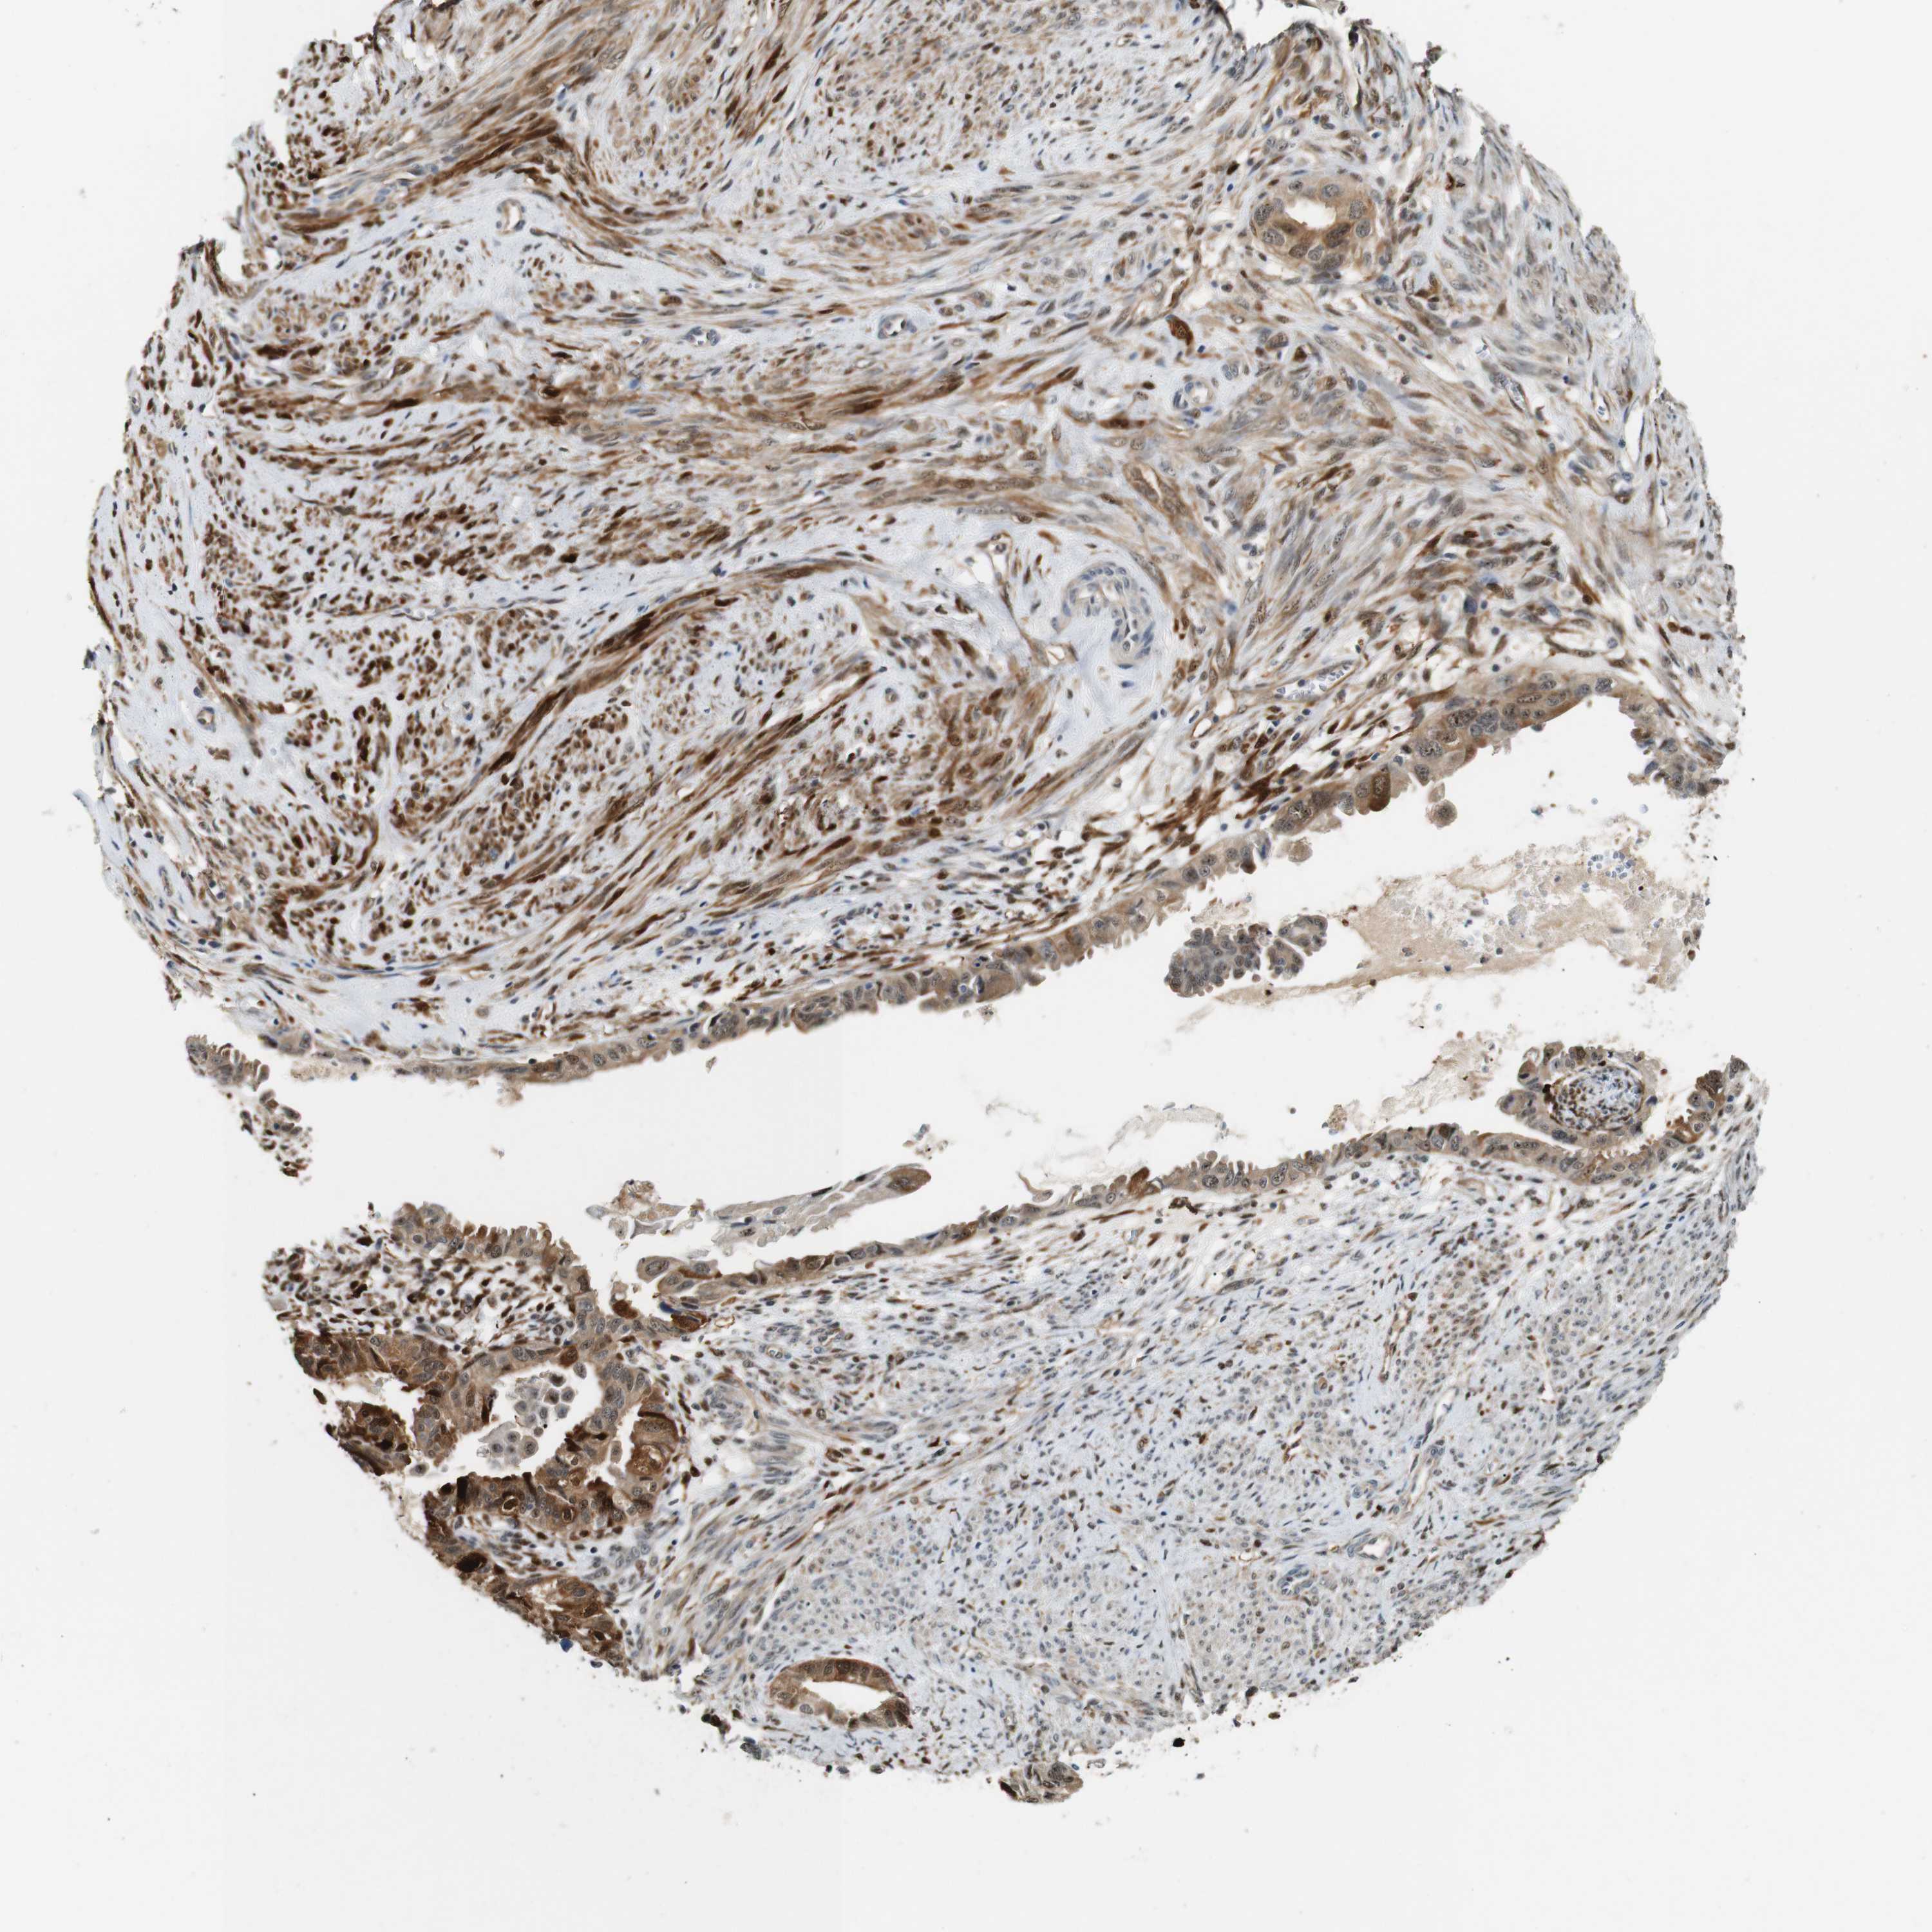

CERVICAL CANCER - Protein expressioni

A mouse-over function shows sample information and annotation data. Click on an image to view it in a full screen mode. Samples can be filtered based on level of antibody staining by selecting one or several of the following categories: high, medium, low and not detected. The assay and annotation is described here.

Note that samples used for immunohistochemistry by the Human Protein Atlas do not correspond to samples in the TCGA dataset.

Antibody stainingi

Antibody staining in the annotated cell types in the current human tissue is reported as not detected, low, medium, or high, based on conventional immunohistochemistry profiling in selected tissues. This score is based on the combination of the staining intensity and fraction of stained cells.

Each image is clickable and will lead to virtual microscopy that enables deeper exploration of all samples and also displays staining intensity scores, fraction scores and subcellular localization as well as patient and tissue information for each sample.

Antibody HPA014179

Antibody CAB025128

Staining

High

Medium

Low

Not detected

Intensity

Strong

Moderate

Weak

Negative

Quantity

>75%

75%-25%

<25%

None

Location

Nuclear

Cytoplasmic/membranous

Cytoplasmic/membranous,nuclear

Squamous cell carcinoma, NOS

Adenocarcinoma, NOS